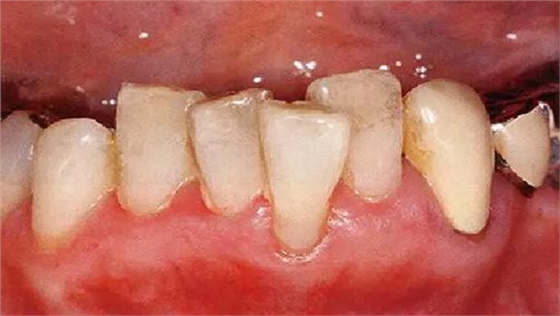

●牙列異常引起的附著喪失

牙列不齊導(dǎo)致被擠出牙弓的牙齒,其牙槽骨、牙齦變薄,很容易引起附著喪失、露出根面。由于刷牙過度會(huì)進(jìn)一步引起牙齦萎縮、根面磨耗、根面齲、牙周炎惡化,需要格外注意(本案例中,牙頸部已經(jīng)做過充填處置)。